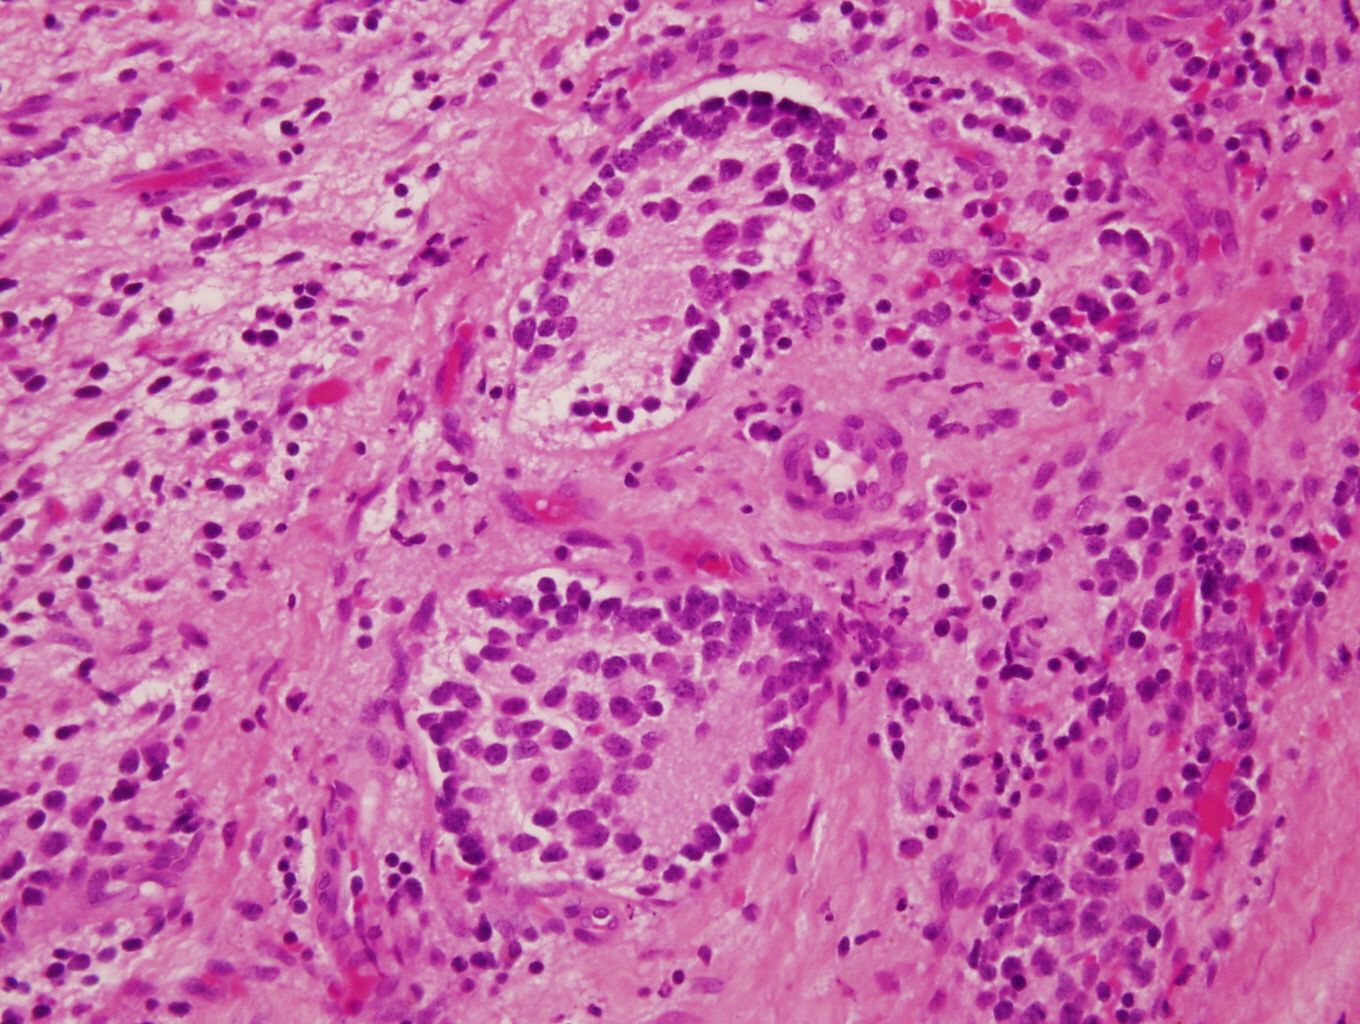

- Architecture: lobular, diffuse / solid, organoid

- Homer Wright pseudorosettes = circular, ovoid, angular zones of pale staining neuritic cell processes surrounded by tumor cell nuclei; may rarely palisade

- Ganglion cells

- Abundant granular eosinophilic cytoplasm (Nissl substance = rough endoplasmic reticulum)

- Distinct cell borders

- Nuclear enlargement, eccentric nuclei, prominent nucleoli

- May see neuromelanin pigment (brown, finely granular; rarely present), cystic degeneration, hemorrhage, dystrophic calcification

Nodular type